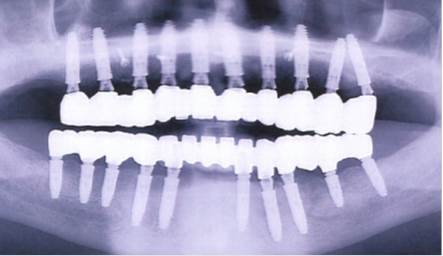

La radio est pas top.

C’est flou...

On détermine mal le niveau d’os autour des implants.

On devine une mauvaise insertion sur les FM.

Niveau des apex d’implants dans les sinus ?

c est beau . il manque 4 implants en bas .

A part ça , en admettant le concept 1 implant par dent , quel intérêt de solidariser le tout ?

et en plus il y en a 3 ou 4 qui n ont pas été connecté à la prothèse ou je rêve?

Le patient souffrait certainement d'une insuffisance en titane.

Le 35 et le 37 chatouillent le nerf mandibulaire. Le type est soit super précis, soit un peu inconscient. Quel intérêt de mettre des implants aussi longs?

Je pencherais pour un Implanto et un “prothésiste “ différents. La prothèse est mal posee, alors que les implants montrent une certaine expérience (parallèles, greffe d’os au maxillaire...)

On a une pano, ok.

Pas de rétros, pas de photos, pas d'occluso, pas de contexte général, âge du capitaine, état de la coque et usure des voiles.

Pas de notions paro, de poches, d'inflammation, de conservation de la gencive attachée, de limites supra ou infra gingivales.

Bref. Si je poste une photo de mon oreille, tu saurais me dire si j'ai une otite?

Beaucoup d'implants certes...

Et pose border line mais adroite.

Effectivement, l'ajustement de l'armature au max semble douteuse, et encore, ça fait un peu artefact pano aussi. Rétros au moins?

on voit pas grand chose sur la mini pano.

Du coup ça peut être un super boulot ou une gentille merdouille.

En tout cas y'a le nombre de clous ;)